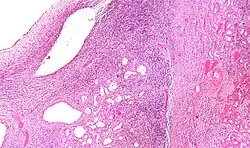

| Micrograph of a cystic nephroma (left of image). Normal kidney is seen on the right. H&E stain. | |

A cystic nephroma, also known as multilocular cystic nephroma, mixed epithelial stromal tumour (MEST) and renal epithelial stromal tumour (REST),[1] is a type of rare benign kidney tumour.

Cystic nephromas are diagnosed by biopsy or excision. It is important to correctly diagnose them as, radiologically, they may mimic the appearance of a renal cell carcinoma that is cystic.[2]

Pathologic diagnosis

The characteristics of cystic nephromas are:

- Cysts lined by a simple epithelium with a hobnail morphology, i.e. the nuclei of the cyst lining epithelium bulges into the lumen of the cysts,

- Ovarian-like stroma that has a:

- Spindle cell morphology, and has a

- Basophilic cytoplasm.